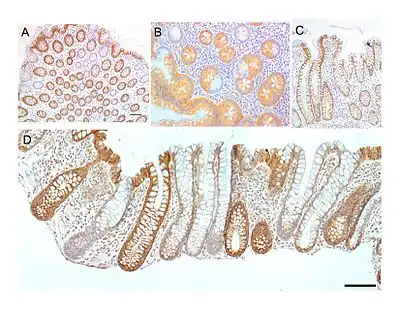

The intestinal glands in the colon are often referred to as colonic crypts. The epithelial inner surface of the colon is punctuated by invaginations, the colonic crypts. The colon crypts are shaped like microscopic thick-walled test tubes with a central hole down the length of the tube (the crypt lumen). Four tissue sections are shown here, two (A and B) cut across the long axes of the crypts and two (C and D) cut parallel to the long axes.

In these images the cells have been stained to show a brown-orange color if the cells produce a mitochondrial protein called cytochrome c oxidase subunit I (CCOI or COX-1). The nuclei of the cells (located at the outer edges of the cells lining the walls of the crypts) are stained blue-gray with haematoxylin. As seen in panels C and D, crypts are about 75 to about 110 cells long. The average crypt circumference is 23 cells.[8] From the images, an average is shown to be about 1,725 to 2530 cells per colonic crypt. Another measure was attained giving a range of 1500 to 4900 cells per colonic crypt.[9] Cells are produced at the crypt base and migrate upward along the crypt axis before being shed into the colonic lumen days later.[8] There are 5 to 6 stem cells at the bases of the crypts.[8]

As estimated from the image in panel A, there are about 100 colonic crypts per square millimeter of the colonic epithelium.[10] The length of the human colon is, on average 160.5 cm (measured from the bottom of the cecum to the colorectal junction) with a range of 80 cm to 313 cm.[11] The average inner circumference of the colon is 6.2 cm.[10] Thus, the inner surface epithelial area of the human colon has an area, on average, of about 995 cm2, which includes 9,950,000 (close to 10 million) crypts.

In the four tissue sections shown here, many of the intestinal glands have cells with a mitochondrial DNA mutation in the CCOI gene and appear mostly white, with their main color being the blue-gray staining of the nuclei. As seen in panel B, a portion of the stem cells of three crypts appear to have a mutation in CCOI, so that 40% to 50% of the cells arising from those stem cells form a white segment in the cross cut area.

Overall, the percentage of crypts deficient for CCOI is less than 1% before age 40, but then increases linearly with age.[7] Colonic crypts deficient for CCOI reaches, on average, 18% in women and 23% in men, by 80–84 years of age.[7]

Crypts of the colon can reproduce by fission, as seen in panel C, where a crypt is dividing to form two crypts, and in panel B where at least one crypt appears to be fissioning. Most crypts deficient in CCOI are in clusters of crypts (clones of crypts) with two or more CCOI-deficient crypts adjacent to each other (see panel D).[7]